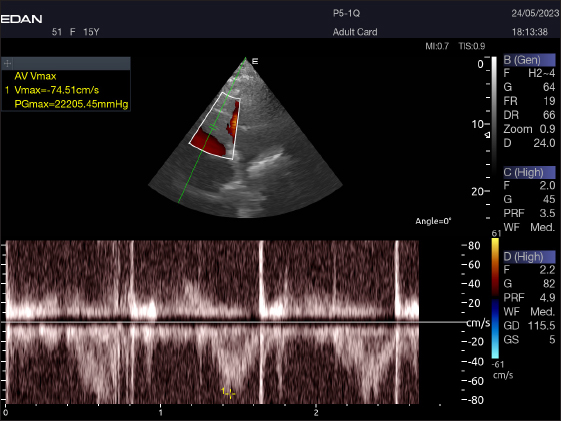

Fig. 2. Short-axis plane M mode (Mushroom shape) of a 16-year-old racing girl camel at level papillary muscle showing left ventricular dimensions (systole and diastole). IVSTd=intraventricular septal wall thickness end-diastolic, LVPWd=left ventricle posterior wall thickness end-diastolic, LVIDd=left ventricular internal dimension, LVIDs=left ventricular internal dimension end-systolic, LVPWs=left ventricle posterior wall thickness, IVSTs=intraventricular septal wall thickness end-systolic, HR=heart rate, EDV=end-diastolic volume, ESV=end-systolic volume, CO=cardiac output, EV=ejection fraction, SV=stroke volume, FS=fractional shortening.

Table 4 provides an overview of pulsed-wave Doppler echocardiographic serial measures in adult racing camels. The pulsed-wave Doppler echocardiographic measurements’ mean values ± standard deviation were recorded for Tv E/A (1.3 ± 0.2 cm2), Mv E/A (1.3 ± 0.2 cm2), Av max (−88.2 ± 25.1 cm/second), and Pv max (−59.2467 ± 17.4 cm/second), as shown in Table 4.

The Mv E/A (Fig. 8), Tv E/A (Fig. 9), and maximum velocity of the aortic valve (Av Vmax) (Fig. 10) were all measured using pulsed-wave Doppler at LPSLAx in all camels. Two cases were observed with mild mitral regurgitation detected through continuous-wave Doppler, but the regurgitation was not considered significant (Fig. 11).

Fig. 10. Normal flow of the aortic valve is demonstrated by left caudal–parasternal spectral PWD Doppler in a 20 years old camel.